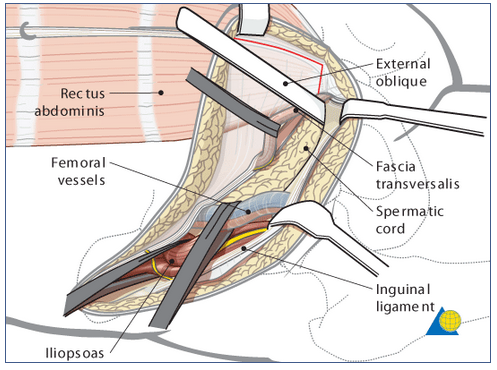

3 windows of ilioinguinal approach

Medial window

medial to external iliac artery & vein

Middle window

between external iliac vessels and the iliopsosas

Lateral window

lateral to iliopsoas (iliopectineal fascia)